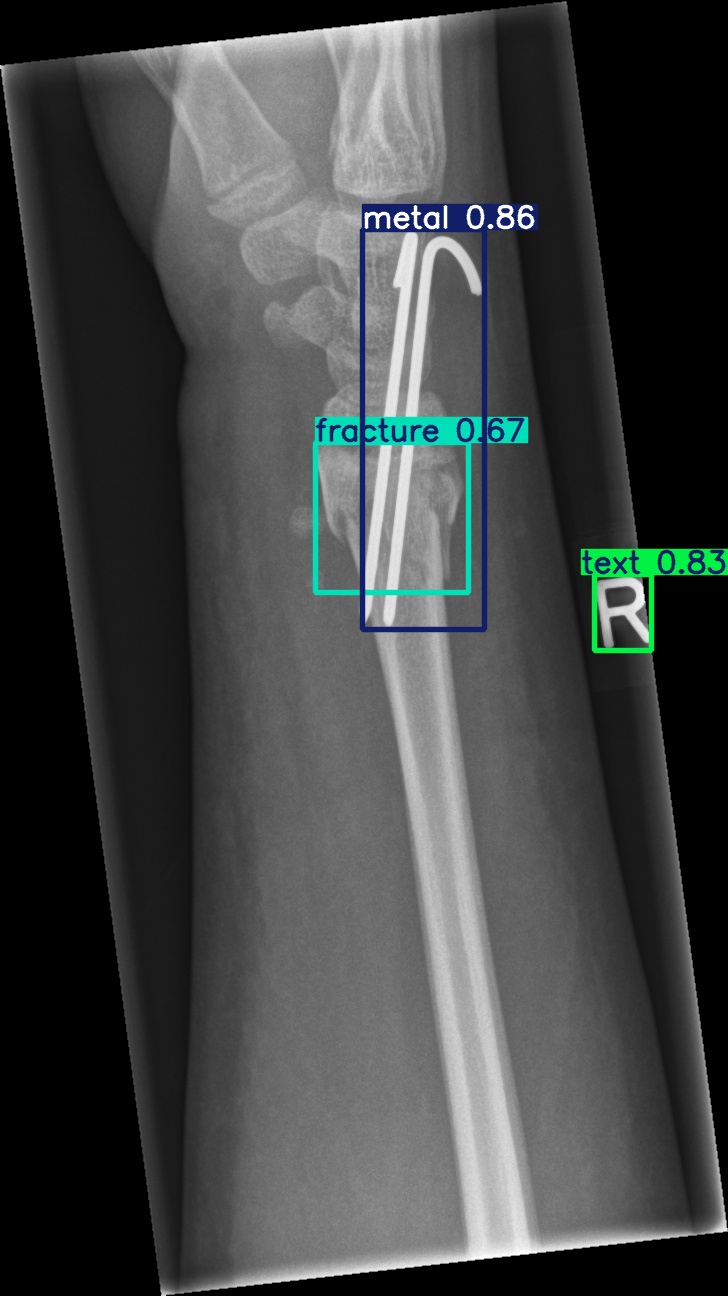

Figure 8: Sample of five images from the GRAZPEDWRI-DX test set, displaying ground-truth and predicted bounding box annotations: (a-e): ground-truth annotations, (f-j): YOLOv11l annotations, and (k-o): G-YOLOv11 annotations.

Table 4: Confidence scores predicted by YOLOv11l and the proposed G-YOLOv11l detectors for five images from the GRAZPEDWRI-DX test set, PR: pronator sign, FP: False positive.

Figure number Class name Confidence score predicted Confidence score predicted

by YOLOv11l by our G-YOLOv11l

8(a) soft tissue, fracture, metal, text -, 0.670.67, 0.860.86, 0.830.83 -, 0.700.70, 0.890.89, 0.840.84

8(b) fracture, text 0.780.78, 0.710.71 0.790.79, 0.730.73

8(c) fracture, text 0.820.82, 0.780.78 0.810.81, 0.790.79, (FP: pr 0.44)0.44)

8(d) fracture, fracture, text 0.770.77, 0.700.70, 0.880.88 0.760.76, 0.520.52, 0.890.89

8(e) fracture, periosteal reaction, text 0.760.76, 0.690.69, 0.760.76 0.750.75, 0.600.60, 0.760.76

The results in Table 4, derived from Figure 8, compares the confidence scores predicted by YOLOv11l and G-YOLOv11l detectors for five test images from the GRAZPEDWRI-DX dataset. Figure 8 contrasts ground-truth annotations with predictions from YOLOv11l and G-YOLOv11l. G-YOLOv11l shows slight improvements, such as higher confidence scores for "fracture" and "metal" in Figure 8(a) (0.700.70 and 0.890.89 vs. 0.670.67 and 0.860.86) and for "text" in Figure 8(b) (0.730.73 vs. 0.710.71). However, limitations include false positives, such as for "pronator sign" in Figure 8(c) (score 0.440.44), and lower confidence for some instances, as seen in Figures 8(d) and 8(e). While G-YOLOv11l demonstrates competitive performance, further refinements are required to improve its robustness.